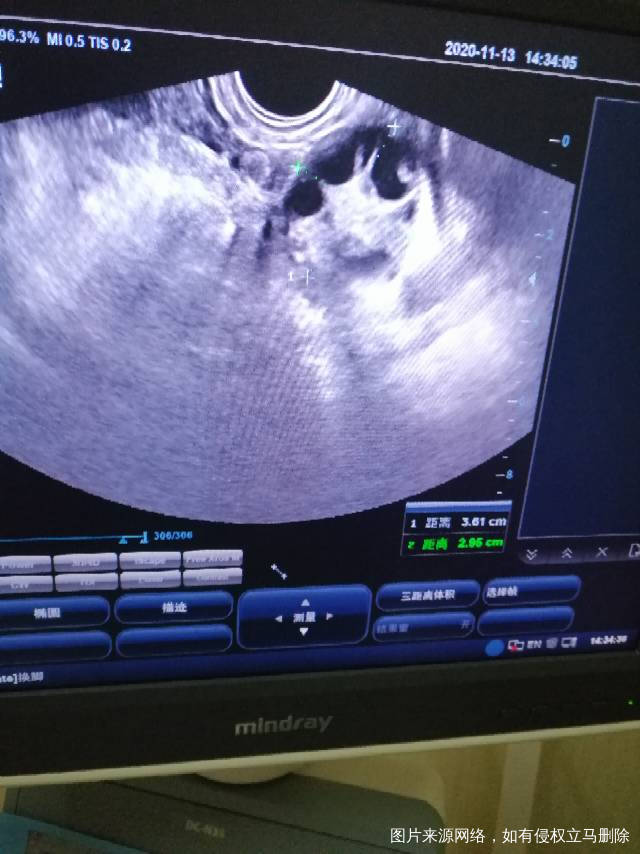

多囊泌乳素高现在都调正常了上个月促排卵也破了